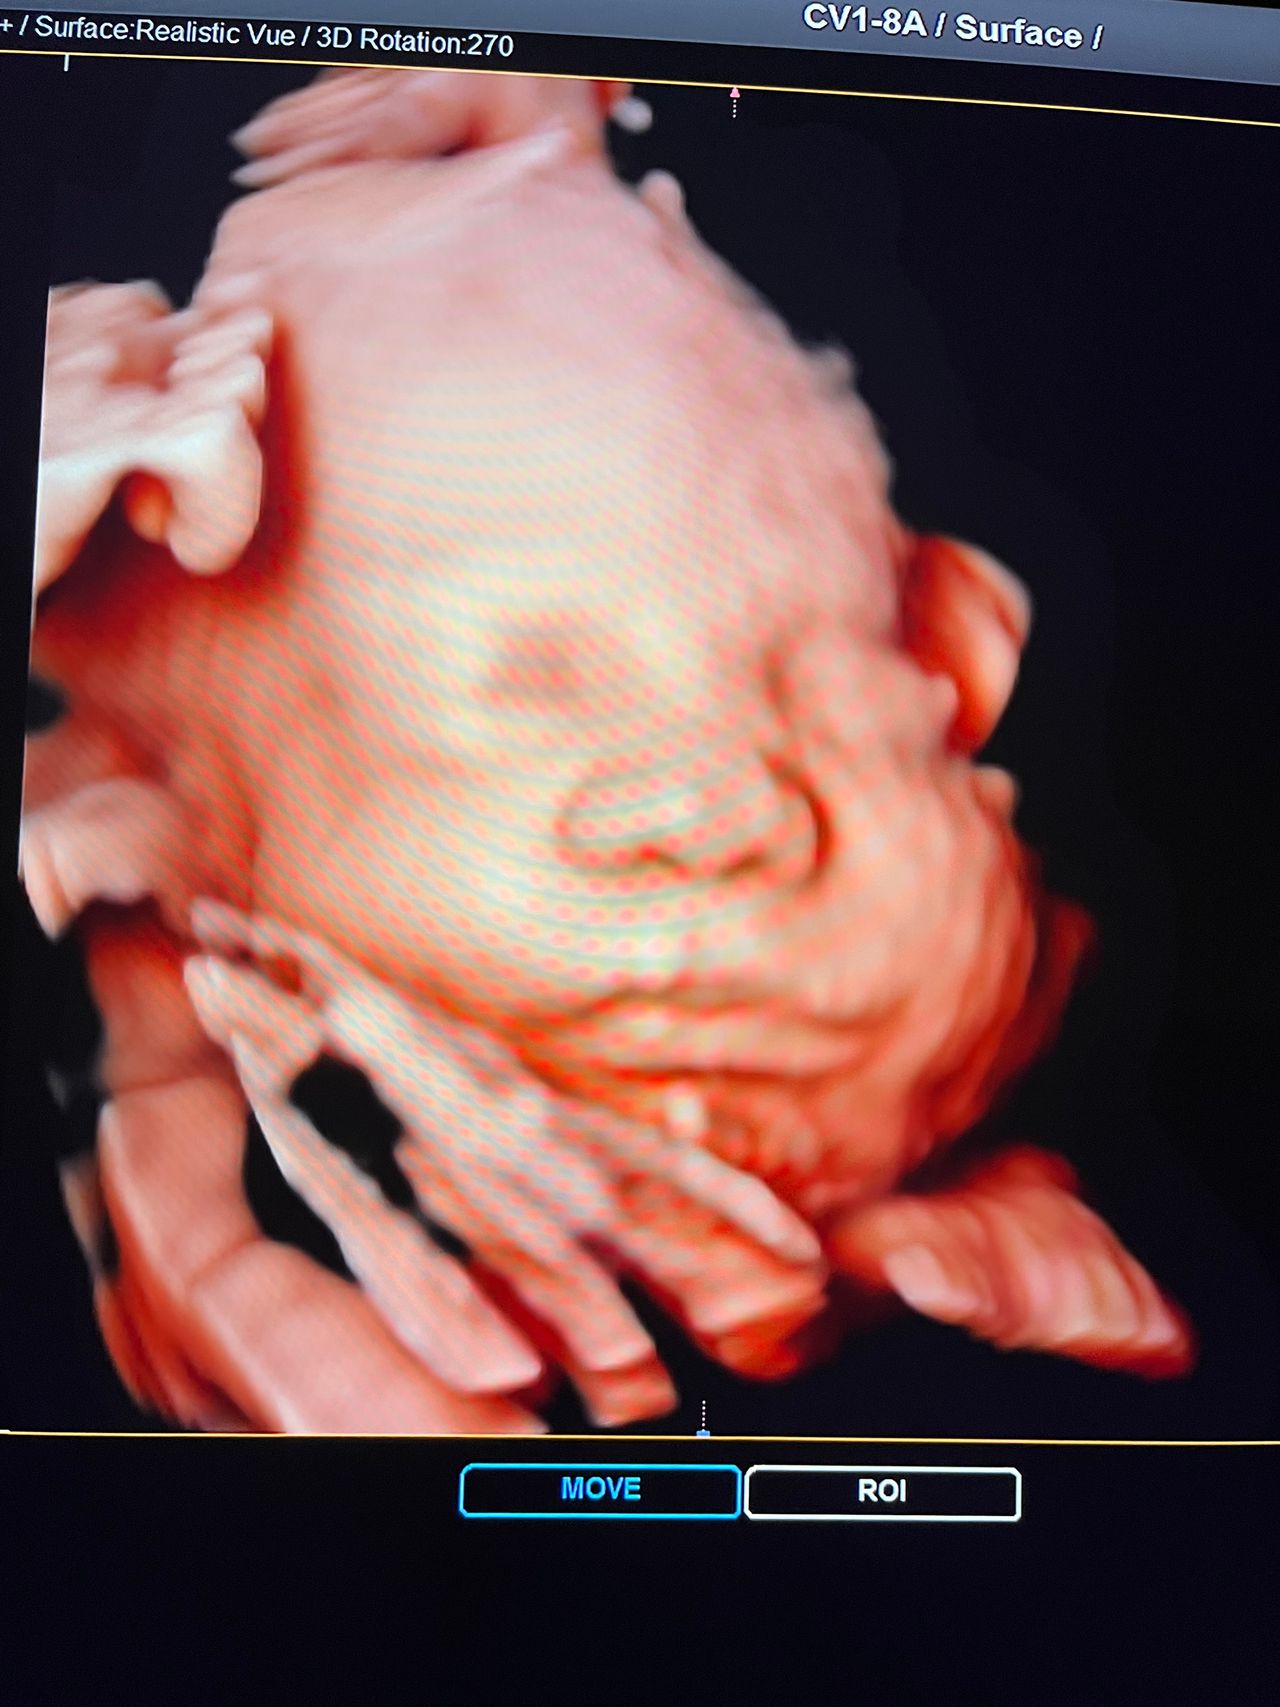

Attualmente lavoro come Dirigente medico nella SC di Ostetricia e Ginecologia dell'Ospedale Michele e Pietro Ferrero di Verduno, mi occupo prevalentemente di screening prenatale, ecografia ostetrica del I trimestre( misurazione translucenza nucale,NT), ecografia morfologica del II trimestre, ambulatorio pregresso taglio cesareo, ecografia ostetrica 3D. Seguo le gravidanze fisiologiche e quelle ad alto rischio , presto servizio in sala parto. Eseguo visite ginecologiche di I-II livello in regime ambulatoriale, counseling contraccettivo ed eventuale prescrizione pillola, inserimento spirale (IUD), dispositivo sottocutaneo (Nexplanon).

Foto e video